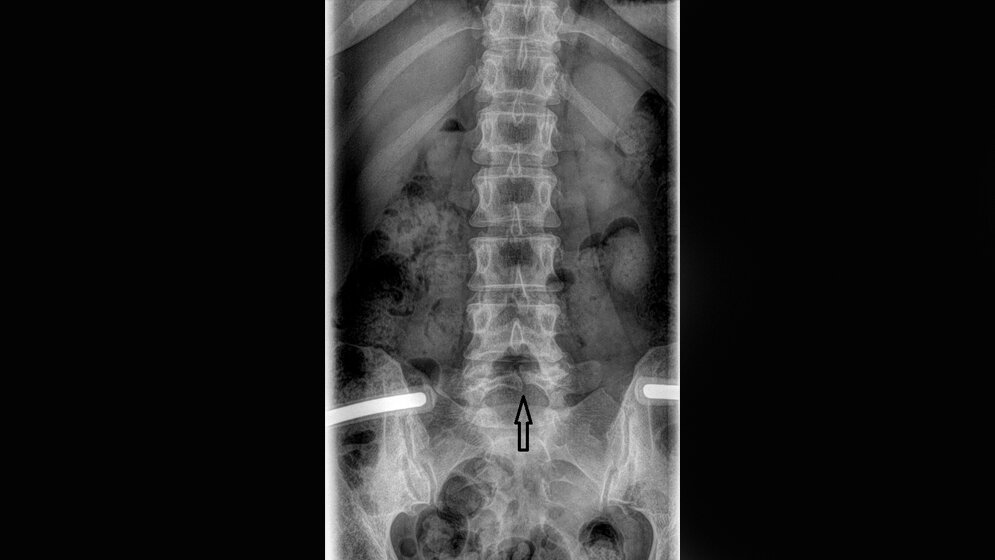

Die Spina bifida ist eine angeborene Veränderung mit inkomplettem Verschluss der Wirbelsäule, bedingt durch einen knöchernen Defekt, in der Mittellinie des Wirbelbogens gelegen. Die Patienten mit Spina bifida occulta sind meist asymptomatisch ohne künftige Verschlechterung des Status und brauchen keine Therapie.

Spina bifida is a congenital disorder with incomplete closure of the spinal column due to a bony vertebral defect. Spina bifida occulta is characterized by a bony defect of the vertebral arch. The patients with spina bifida occulta are often asymptomatic with no future complications and do not require treatments.